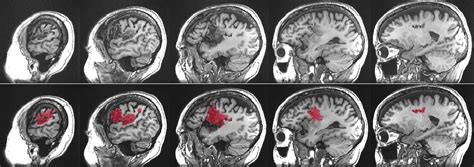

Alright guys, let’s break down aphasia in more detail. So, aphasia isn’t just one single thing; it’s a spectrum of language disorders. The core issue is that the brain’s ability to process language has been disrupted. This usually happens when there’s damage to specific areas of the brain, most commonly the left hemisphere, which is dominant for language in most people. The most frequent culprit behind this damage is a stroke , where blood flow to a part of the brain is interrupted, causing brain cells to die. Other causes can include traumatic brain injuries (like from a car accident or a fall), brain tumors, infections, or even progressive neurological diseases like dementia. The specific type and severity of aphasia depend heavily on the location and extent of the brain damage. It’s crucial to remember that aphasia does not affect a person’s intellect. Someone with aphasia can still think, reason, and feel emotions just as they did before. The difficulty lies purely in the expression and comprehension of language. This is a really important distinction to make because it can be disheartening when people wrongly assume aphasia means a loss of cognitive abilities. The frustration for individuals with aphasia often stems from this very misunderstanding. They might know what they want to say, but the words just won’t come out, or they might struggle to grasp what others are saying, even though their hearing is perfectly fine. It’s like having a word on the tip of your tongue, but it’s permanently stuck there. This can lead to significant emotional distress, isolation, and a feeling of being disconnected from the world. Understanding these nuances is the first step towards providing effective support and fostering an environment where communication, in whatever form it takes, can flourish.

So, how does aphasia actually happen? The main reason, as we touched upon, is damage to the brain’s language areas . Let’s chat about the most common causes. Strokes are the big one, guys. They happen when blood supply to a part of the brain is cut off (ischemic stroke) or when a blood vessel bursts in the brain (hemorrhagic stroke). These events can quickly damage brain cells, and if those cells are involved in language processing, aphasia can result. Think about it: the brain is incredibly complex, with different regions specializing in different tasks. The parts responsible for understanding grammar, retrieving words, forming sentences, and interpreting meaning are all susceptible to stroke damage. Following stroke, it’s common for people to experience aphasia, and the type can vary widely. Another major cause is traumatic brain injury (TBI) . This can result from a blow to the head, a fall, or any incident where the brain experiences sudden, forceful movement. TBIs can cause widespread damage, and if the language centers are hit, aphasia is a likely outcome. This is why proper safety measures, like wearing helmets, are so important! Brain tumors can also lead to aphasia. As a tumor grows, it can press on or invade brain tissue, disrupting normal function. If the tumor is located in or near the language areas, it can impair communication. Similarly, brain infections , such as encephalitis (inflammation of the brain), can cause swelling and damage that affects language abilities. Less commonly, but still a possibility, are progressive neurological conditions . Diseases like Alzheimer’s disease and other forms of dementia can gradually damage brain cells over time, and as the disease progresses, it can impact language skills, leading to various forms of aphasia. It’s also worth noting that aneurysms (weakened spots in blood vessel walls) or arteriovenous malformations (AVMs) (abnormal tangles of blood vessels) in the brain can rupture, leading to bleeding and subsequent aphasia. The key takeaway here is that anything that disrupts the normal functioning of the brain’s language network can potentially lead to aphasia. Understanding these causes helps us appreciate the vulnerability of our brain and the importance of seeking prompt medical attention if any of these events occur.

Now, let’s get into the nitty-gritty of aphasia types. It’s super important to know that aphasia isn’t a single condition; it presents in different forms, each with its own set of challenges. The classification usually depends on which part of the brain is affected and how it impacts both expressive (speaking/writing) and receptive (understanding/reading) language. We’ve got the big players here, and understanding them can really help in recognizing the specific difficulties someone might be facing. First up, we have Broca’s aphasia , often called expressive or non-fluent aphasia. People with this type usually understand language pretty well, but they have a really hard time producing it. Their speech might be slow, effortful, and often consists of short, broken phrases. They might omit small words like ‘the’ or ‘is’, making their sentences sound like telegraphic messages. It’s like they have the words in their head but struggle immensely to get them out. Then there’s Wernicke’s aphasia , also known as receptive or fluent aphasia. This is the flip side. People with Wernicke’s aphasia can speak fluently, but their words often don’t make sense. They might produce long, rambling sentences filled with made-up words (neologisms) or incorrect words (paraphasias). They often have significant difficulty understanding spoken or written language, and they may not even be aware that what they’re saying is nonsensical. It’s a really disorienting experience for them. We also have global aphasia , which is the most severe form. This occurs when there’s extensive damage to the language areas of the brain. Individuals with global aphasia have severe impairments in both speaking and understanding language. Their ability to read and write is also greatly affected. Communication can be extremely limited, making everyday interactions a significant hurdle. Then there are other types, like anomic aphasia , where the main problem is finding the right words. People with anomic aphasia can speak fluently and understand language well, but they struggle with word retrieval, often pausing frequently or using general words like ‘thing’ instead of specific nouns. Conduction aphasia is another interesting one where individuals have difficulty repeating words or sentences, even though their comprehension and spontaneous speech might be relatively intact. Finally, transcortical aphasia includes subtypes (sensory, motor, mixed) that affect specific aspects of language production and comprehension while preserving other abilities, like the capacity to repeat. Recognizing these different types is key for tailoring therapy and support to meet the unique needs of each individual affected by aphasia.